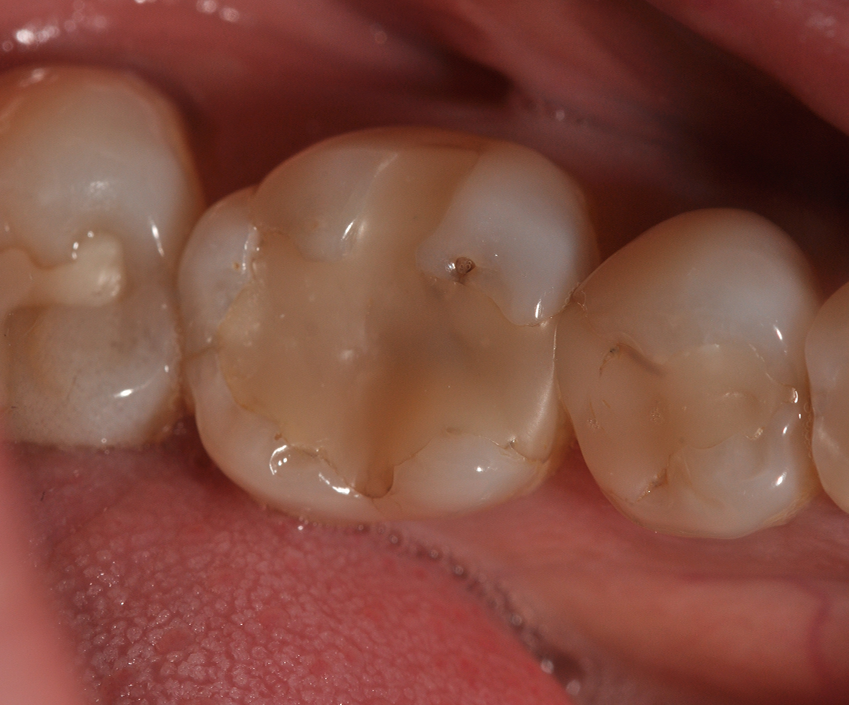

A 36-year-old female patient visited a private office for an annual checkup. Clinical evaluation showed a Class II composite restoration presenting marginal leakage and lack of anatomy and esthetics in tooth #30 (Fig. 1). Due to the patient’s needs and considering the amount of remaining tooth structure, the treatment planned was a direct restoration with resin composite.

Fig. 1 Fig. 2